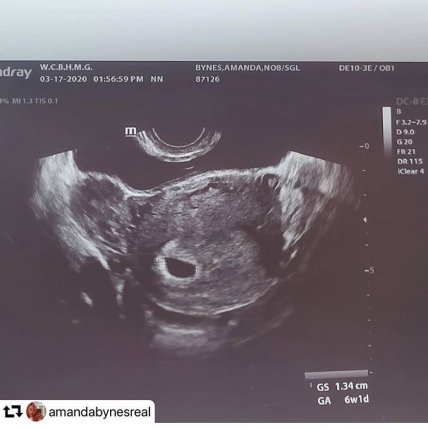

33-летняя актриса Аманда Байнс беременна. Об этом она и ее жених Пол Майкл сообщили на своих страницах в Instagram, опубликовав снимки УЗИ. Но затем оба удалили эти публикации.